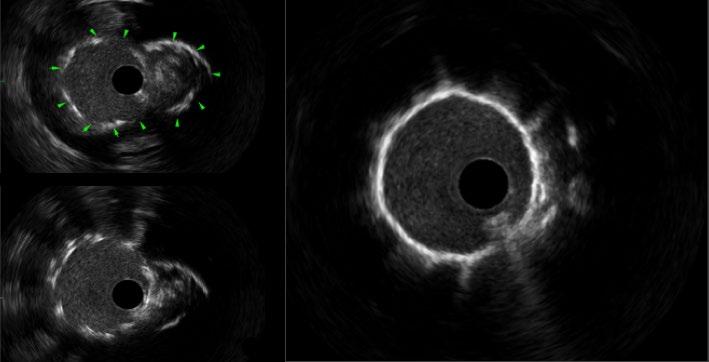

do a similar analysis in Europe, it's probably 80% receiving alcohol ablation, and if you go to Asia, the percentage undergoing alcohol ablations is even higher. In general, I think there has been a larger adoption of minimally invasive procedures in Europe and Asia, partly for spiritual reasons in Asia, and in Europe, I think it’s more due to lack of availability of surgical centres. Whereas, in the USA, there are many large centres that have shepherded hypertrophic cardiomyopathy care for many, many decades, and so surgery continued on as a primary modality. I do think that in the appropriate hands, the mortality rate is better and the efficacy is similar with alcohol ablation (in the appropriate patients), and so the only detriment really is the pacemaker rate. Mostly, patients over the age of 50 or 60 years typically don't mind this, because if they get a pacemaker at that age, it's usually not too much of a burden. It also allows monitoring of the patient for atrial fibrillation or other arrhythmias that might prevent sudden cardiac arrest down the line.

The problem with both of these procedures is that they are very hard to teach and, like any other procedure, you need to do a certain number of them to maintain the credibility and expertise over time. So, in the 2011 American Heart Association (AHA) guidelines, we recommended that institutions should do 10 procedures a year to maintain certification, credibility, and expertise, but very few places can do that. In our heyday, we were doing about 40 alcohol ablations and 30 myectomies a year here. Now, with the use of mavacamten and other cardiac myosin inhibitors, the volume of procedures done will be cut in half. So, one of the main challenges is,

how do you set up major centres to offer this? With this in mind, we developed a course. It's over 10 years old now; we had a break during the COVID-19 pandemic, but we've done roughly seven courses since its inception, and they have been very popular. The only way to learn this procedure is to see a few of them at once. We usually have about three cases over the course of 2 days, and then, through didactics, we discuss all of the alcohol ablation details, including preprocedural and intraprocedural planning and post-procedure management. We then take attendees through live cases, where we go through the procedure step-by-step on actual patients. Finally, we end with critical care rounds, where we look at the patients afterwards and discuss their ECG, pacemaker requirements, and how to manage them before they go home. It's a very comprehensive course and we’ve probably trained over 100 people who have all gone out to do the procedure. So, it does work and now they have the experience. Even if they don't do 10 per year, they have a network of individuals who they can run cases by and refresh their ideas on the tools and the equipment needed, and how to plan for that procedure for that given patient.

I do think that surgeons should do the same thing. They have not developed a course in this space. I have advised that they do because I think that both these procedures are very important and valuable for the population, including in Europe. About 10 years ago. Barry Maron wrote a paper entitled, ‘Bring Septal Myectomy Back for European Patients’,1 which was essentially a call to action, highlighting that we do need capable surgeons out there to do this. I would be an advocate for that as well.

In the surgery field, they train in their fellowships, but then afterwards there's not a whole lot of training opportunities, from what I can see. I think it's more in the mindset of interventional cardiology to proctor other people and spread these procedures more broadly. But I think within the surgical field, they tend to rely on their societies and their training pipeline, and not necessarily courses like these. Additionally, they tend not to train their competition. Now, you can say the same thing for interventional cardiology, but I specifically bucked that trend by saying: “I'm going to train people to compete with me.” That’s because the greater good is more important. I know it's easy to say that, but the truth is that in any field, people tend to hold on to their trade secrets. Now, with that being said, I will say that our surgeons were trained by the Mayo Clinic surgeons, but that was through a personal relationship. Though I think the Mayo Clinic surgeons have done a good job of going out and training individual surgeons at other institutions, and I give them credit for that, I do wish that somebody would take the mantle and develop an actual course. We did think about expanding our course to include surgeons, but again, it depends on funding and the availability of surgeons who are willing to do it.

Q3 Can you tell us about your book, ‘Lindsay's Big Heart’. How does improving patient/family health literacy correlate with treatment adherence and outcomes in the HCM population?

I'm a creative person; I like doing different things and coming up with new ideas. This idea came out of a desire to spread HCM awareness a lot broader, and

books have a way of spanning globally. In other words, they can be translated to other communities. And actually, we've had some interest from the HCM Foundation in Europe, as well and other places, to translate the book.

The reason for spreading awareness for HCM is that most patients with HCM seek medical attention when they are middleaged, which means that they have probably been living with their HCM for decades. It's known to start in puberty and teenage years, so there's usually a long latency period where they have the disease but no symptoms. We would like to catch people at that stage where they're developing hypertrophy but don't have symptoms, so we can start getting them treated earlier and possibly prevent progression.

The second issue is that a lot of these people have kids, and they have no idea how to talk to their kids about this disease. I feel like if a woman has breast cancer, they sit their daughter down, tell them about breast cancer, and why they need to have mammographies. However, we don't do the same for other genetic diseases, like HCM, and because of that, I wanted to have a tool that parents can read to their kids while they're young, before the HCM even develops, if it even develops. That way,

when they get older and their ECG looks suspicious or they have symptoms, they will not be scared to tell their doctor that there is HCM in their family. At the moment, I do not see that happening, and the only way to get that to happen is to educate people at an age where they can see that this is running in their family and not be scared of it. That's the second part of it, which is something the book really addresses: how to digest this disease as one thing in your family and not be scared of it.

We would like to catch people at that stage where they're developing hypertrophy but don't have symptoms

What you see is a young girl go through this and lead a very happy, normal life. It shows that none of the testing was scary, and she can go on to do all the things she wants to do; she just happens to have this bigger community of physicians, parents, and other people who now know her and how to protect her, including having defibrillators in the school and people around her knowing CPR. So, I think the

book comes out of this genuine idea to have a resource for kids where they can be curious and understand their disease in a way that makes sense to them.

At the same time, we didn't want to water the information down. We made sure that the book has pictures that are accurate, and every picture included has educational value, including having defibrillators visible and showing the different testing that people get throughout their evaluation and management. I spent a lot of time on additional pages for parents at the end: two pages on how to keep your kids safe, and two pages that define all the complicated medical terms that even parents wouldn't understand, so that they're prepared when they go into their doctor's appointment. So, there's a little bit of a dictionary at the end to help people understand the top 20 words that come up in this disease. I wanted to make sure the book really spanned both parents and kids.

If we have the energy and funding, we would like to translate the book into different European languages, certainly Spanish and French, and then eventually Mandarin and Arabic. I'm not sure what else, but those probably cover a large portion of the world. HCM is a disease that spans both genders and all races, and happens

in rich communities and poor communities; I do want to get it to all kids of the world. A 19 USD book is something that you can get everywhere, including for free in libraries, whereas actual healthcare is not quite as egalitarian.

Are you planning on writing any other books?

I’m not writing any at the moment, because I have a lot on my plate right now, but the publisher that we have has already mentioned that they would love to have more of a series. Lindsay Davis is one of my friends with HCM and this book is modelled after when she was around 8 years old, and Kiran, the boy in it, is my son, and it's modelled after when he was also 8 years old. He's sort of the ‘smarty pants’ kid who teaches her a lot whilst in the hospital after having a false alarm. So, I think one of the ideas was to have a Lindsay and Kiran series, where they can each be the protagonist, depending on the disease state. For example, the next book could be about Kiran's peanut allergy. There's so much opportunity to talk about something like that and make different conditions and diseases less scary.

Q4Your work on the 2019/2022 universal cardiogenic shock definitions revolutionised trial design. How have these criteria impacted mortality stratification in recent studies like RECOVER III?